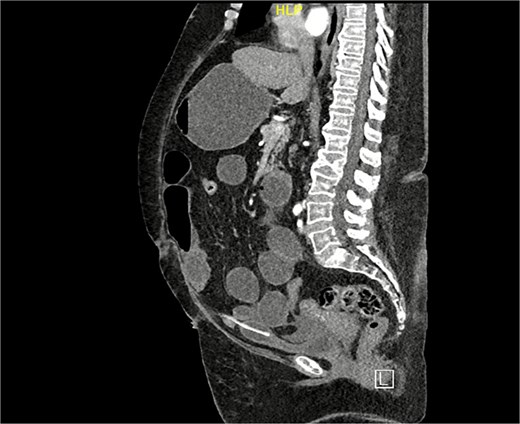

A computed tomography (CT) scan of the abdomen and pelvis was performed for further evaluation. The coronal view demonstrated a markedly distended stomach, mesenteric fat stranding with a small amount of free fluid, along with bowel dilation involving the mid and proximal small bowel loops (measuring up to 4 cm) with a transition zone at the site of bowel twisting over the suprapubic catheter (Fig. 1). On the sagittal view, the suprapubic catheter was seen positioned correctly within the bladder (Fig. 2). The bowel demonstrated normal enhancement, with no evidence of wall thickening, pneumatosis intestinalis, or pneumoperitoneum.

CT scan coronal view: Demonstrating distended small bowel loops consistent with small bowel obstruction, with a transitional zone at the twist of bowel over the suprapubic catheter.